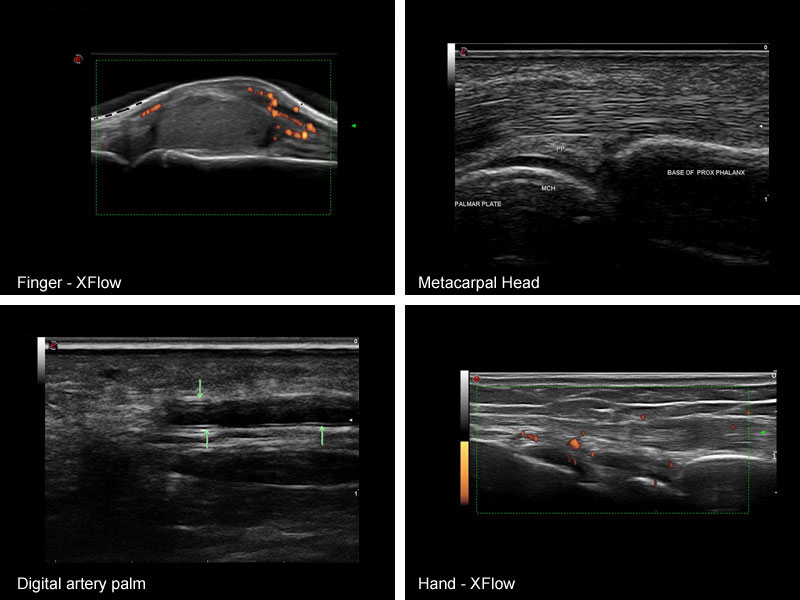

Nelle artriti lo studio ecografico dell’articolazione permette al Reumatologo di valutare, con accuratezza maggiore rispetto all’esame clinico, la presenza di versamento intra-articolare e soprattutto di ipertrofia della membrana sinoviale. Cosa ancora più importante l’utilizzo della metodica PD permette, come avevamo accennato in precedenza, di valutare la presenza e l’entità di uno stato infiammatorio articolare, permettendo in questo modo di valutare l’attività di malattia in maniera più oggettiva rispetto all’utilizzo di indicatori clinimetrici.

Tramite uno studio ancora più accurato un Reumatologo esperto è inoltre in grado con l’ecografia di distinguere con relativa sicurezza diversi “pattern” di proliferazione sinoviale o la presenza di panno sinoviale attivo ed erosivo al di sotto del profilo di corticale ossea (caratteristici di Artrite Reumatoide), riuscendo in questo modo anche a dare un’indicazione di severità di malattia e di prognosi, oltre che di attività. La sua facile accessibilità e la rapidità di utilizzo le permettono in questo modo di essere estremamente utile anche nel “follow-up” della malattia nel tempo, permettendo allo specialista di monitorare l’efficacia delle diverse strategie terapeutiche in maniera precisa ed oggettiva. L’ecografia permette inoltre di valutare in maniera efficacia la presenza di flogosi a carico delle strutture tendinee, che può essere presente sia come estensione della flogosi articolare che in assenza di essa (come ad esempio in caso di dattilite, tipica dell’Artrite Psoriasica), che a livello delle entesi, interessamento tipico delle Spondiloentesoartriti.

In questi ultimi anni l’indagine ecografica ha acquistato sempre più importanza all’interno della diagnostica delle patologie reumatologiche. I vantaggi della metodica ultrasonografica rispetto alle altre metodiche di imaging risiedono principalmente nella sua facile accessibilità e nella rapidità di esecuzione. Infatti benché un esame ecografico completo di un’articolazione richieda tempo, un semplice approfondimento diagnostico ultrasonografico, basato sui riscontri dell’esame obiettivo permette al Reumatologo esperto di discriminare tra numerose problematiche articolari, risultando in questo modo un utilissimo complemento alla visita classica. Infatti, nonostante un accurato esame obiettivo permetta già di per sè di discriminare con buona probabilità tra le varie problematiche articolari, l’esecuzione di un rapido controllo ecografico è in grado spesso di confermare con certezza il sospetto diagnostico, creando in questo modo un’importante sinergia tra le due metodiche, che non sono quindi da considerarsi in antitesi. Un altro grande vantaggio esclusivo della metodica ecografica è la possibilità, essendo l’esame in “real time” di eseguire un esame dinamico, che risulta essere fondamentale nello studio di determinate componenti articolari, come ad esempio i tendini, ma che risulta indispensabile anche per valutare i rapporti che intercorrono tra le varie strutture dell’articolazione o tra queste ed eventuali lesioni come cisti o calcificazioni. (IMG) In questi casi infatti l’utilizzo dell’esame dinamico, ed in particolare facendo muovere l’articolazione al paziente, è possibile valutare il grado di mobilità della lesione nei confronti dei piani superficiale e profondo o ancora di valutare la tipologia di contenuto di una lesione valutandone la comprimibilità. L’ecografia ci permette di eseguire un’indagine di tipo “funzionale” tramite lo studio con Power Doppler (PD), che studia l’entità della vascolarizzazione di un tessuto permettendo in questo modo al Reumatologo esperto di discriminare con buona sicurezza tra problematiche di tipo meccanico e di tipo infiammatorio, condizione di importanza fondamentale per la valutazione dell’attività di malattia in pressoché tutte le malattie reumatologiche. In ultimo, ma non meno importante, l’ecografia può essere utilizzata anche a scopo terapeutico, ed in particolare per “guidare” l’operatore nell’esecuzione di artrocentesi ed infiltrazione, consentendo un grado di precisione assolutamente non paragonabile all’esecuzione “a mano libera”, specie quando è necessario operare su articolazioni profonde o su raccolte di piccole dimensioni.